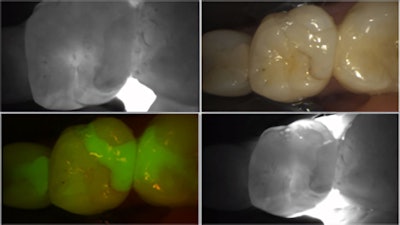

The Catapult Product Evaluation Team, a group of dentists who apply new dental products and innovations into their already active and busy practices, was recently introduced to the DIAGNOCam by KaVo. This is a full-vision high-definition camera with three modes. The intraoral mode is similar to most intraoral camera features, but this camera has HD clarity. The two other modes, fluorescence and near-infrared transillumination, are geared more toward diagnosis. The fluorescence mode allows the practitioner to see caries, plaque, and occlusal attrition with greater clarity than with a traditional intraoral photo. Images in all three modalities can be captured simultaneously and displayed side by side.

Figure 7: Evaluating the marginal seal of an old resin filling. Transillumination shows some leakage, and the red fluorescence signal shows bacterial activity.Figure 7: Evaluating the marginal seal of an old resin filling. Transillumination shows some leakage, and the red fluorescence signal shows bacterial activity.

The transillumination mode, however, for me, was the game changer. The DiagnoCam’s special tip emits near-infrared light at the gingival level, from both the buccal and lingual aspects. The near-infrared light transmits through healthy enamel toward the camera, which has a corresponding bright, white appearance on the resulting image. Areas of carious or demineralized enamel scatter the light, resulting in a corresponding darker region.

Figure 8.Figure 8.

Using the same radiograph from above (Figure 8), I transilluminated the questionable areas, yielding highly accurate discernment of the extent and location of various cavities.

Figure 10: This is the interproximal space between teeth #20 and #21. Notice that both lesions are incipient and do not extend into the dentin. This provided further confirmation that a traditional class II prep would not be appropriate.Figure 10: This is the interproximal space between teeth #20 and #21. Notice that both lesions are incipient and do not extend into the dentin. This provided further confirmation that a traditional class II prep would not be appropriate.